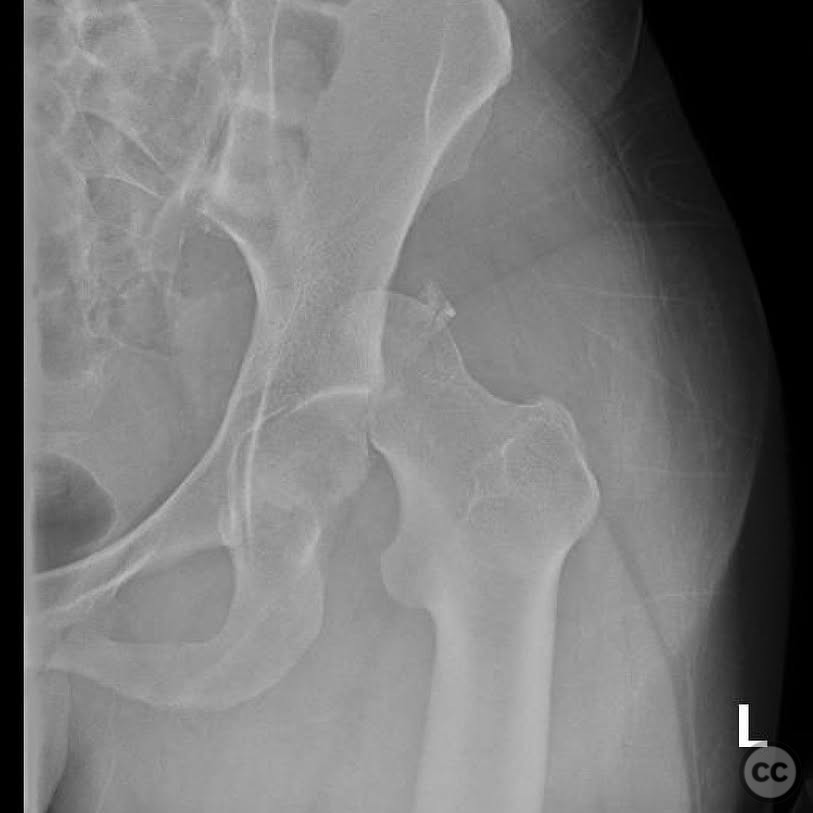

Clinical and radiological findings:  A 33-year-old female involved in a motor vehicle collision presented with a posterior hip dislocation accompanied by a comminuted supra-foveal femoral head fracture, a cranial peripheral posterior wall fracture, and a non-displaced femoral neck fracture. The injury is associated with a risk of sciatic nerve palsy and avascular necrosis (AVN).

Preoperative Plan

Planning remarks:  The preoperative plan involved a Gibson approach with a trigastric slide osteotomy for anterior dislocation to address the femoral head fracture. The intention was to reconstruct the femoral head using a femoral head allograft due to a 20% pie slice defect. The posterior wall was to be addressed through capsulolabral repair with suture anchors and spring plates.